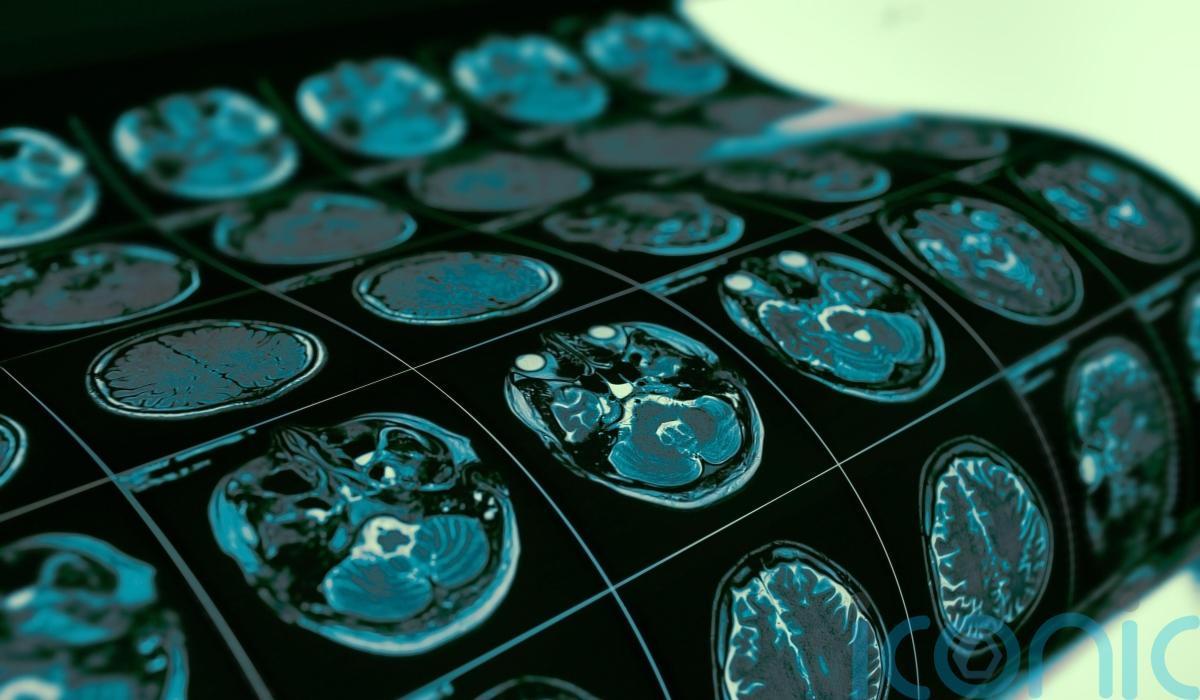

On Monday, he wrote on X to say he had an MRI scan last week and there was still no sign of recurrence.